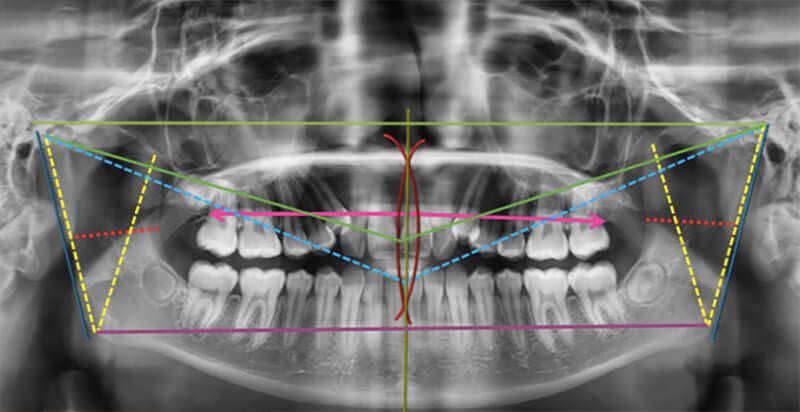

En la radiografía panorámica tenemos 31 dientes presentes, con terceros molares en formación y con tercer molar superior derecho ausente, caninos superiores con patrón de erupción ectópico (figura 7).

Fig. 7 Radiografía panorámica inicio

Se realizó análisis de Levandoski en cual señaló la desviación de la línea media superior e inferior hacia la derecha, por lo tanto, no coincide con la línea media facial.

El cóndilo del lado derecho se encuentra a 2 mm más inferior en relación al cóndilo izquierdo. La altura de la rama derecha es más corta que del lado izquierdo por 2 mm.

El cuerpo mandibular derecho es más corto con 2 mm que el izquierdo.

La línea media superior se encuentra desviada 2 mm a la derecha con la línea facial. Condileon-Gonion presenta una altura igual.

La altura condileon-apofisis coronoides presenta 1mm de diferencia mayor del lado izquierdo. El maxilar superior presenta una inclinación normal.

En el ancho de las ramas la derecha siendo 1mm más ancha que la izquierda (figura 8).

Fig. 8 Trazos análisis de Levandoski los cuales nos muestran con líneas de colores, la discrepancia en medidas entre un lado con relación al otro.